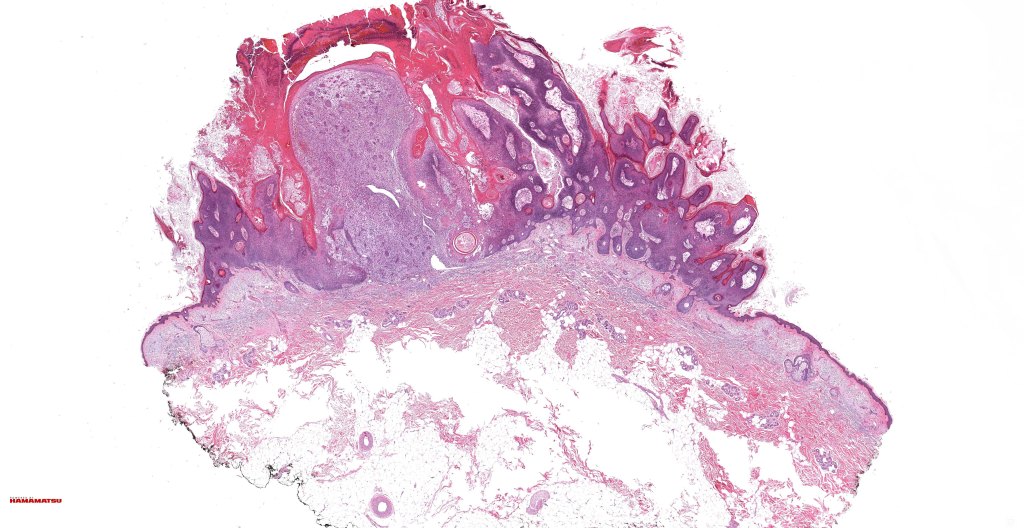

•Often rapidly growing, ulcerated, often large exophytic, nodular tumor

•Biphasic tumor

•Possible epithelial to mesenchymal transition

•Admixture of squamous carcinoma & pleomorphic spindled cell, osteoid, chondroid, MFH-like +/- osteoclast-like giant cells & rarely, smooth muscle, skeletal muscle, myofibroblastic or angiosarcomatous elements